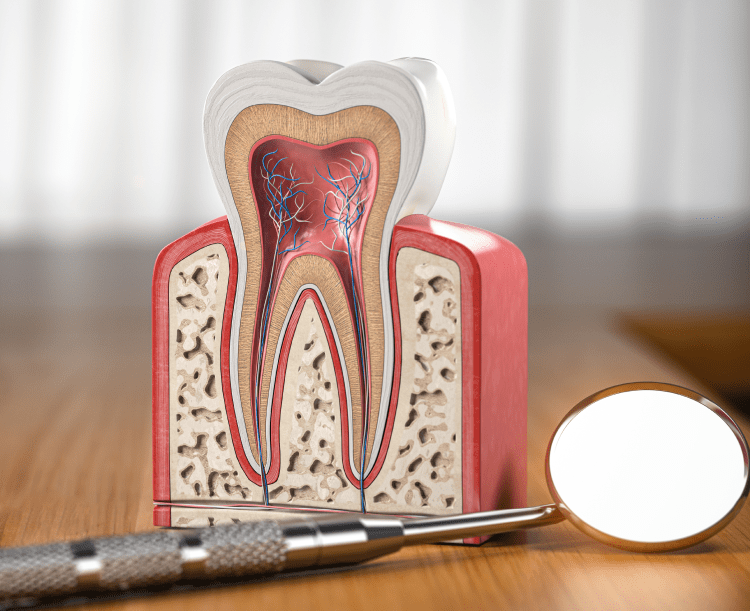

- 口腔外科では、歯や歯肉だけでなく、顎、舌、口腔粘膜など、口の中とその周辺組織の外科的な治療を行います。

親知らずの抜歯は口腔外科で最も多い処置の一つです。埋まっている親知らずや横向きに生えている親知らずなど、複雑な症例にも対応いたします。歯根端切除術は、根管治療で改善が見られない場合や、病巣が大きい場合に行う外科的処置です。

歯牙再植は、わずかでも歯根破折の疑いがある場合に採用する方法で、一度歯を抜いて口腔外で処置を行い、再び元の位置に戻す治療法です。歯冠長延長術や歯肉形成など、審美的な改善を目的とした処置にも対応しております。

- 歯根端切除術とは

- 歯根端切除術は、根管治療で改善が見られない場合に行う外科的処置です。歯肉を切開して歯槽骨を削り、歯根の先端部分と病巣を直接除去します。根管治療では届かない部分にある病巣を取り除くことができます。

- 歯牙再植とは

- 歯牙再植は、一度歯を抜いて口腔外で処置を行い、再び元の位置に戻す治療法です。口腔内では処置が困難な部位でも、口腔外であれば直視下で確実な処置が可能になります。特に歯根破折の疑いがある場合に有効です。